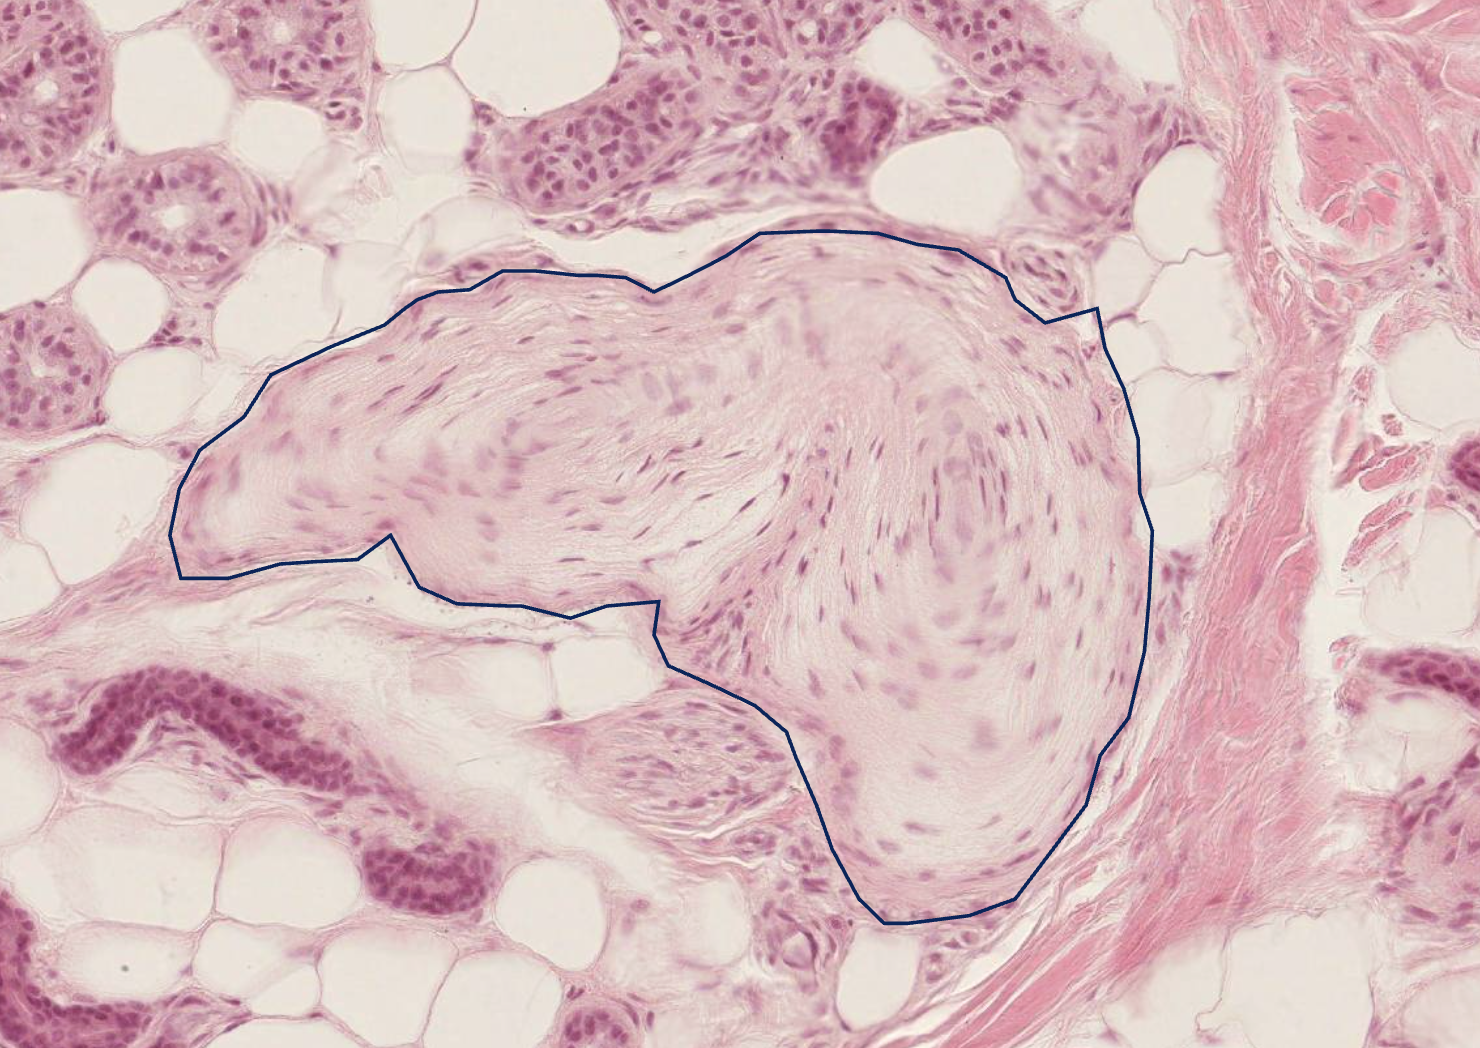

<p>what this</p>

what this

lamellar (Pacinian) corpuscle